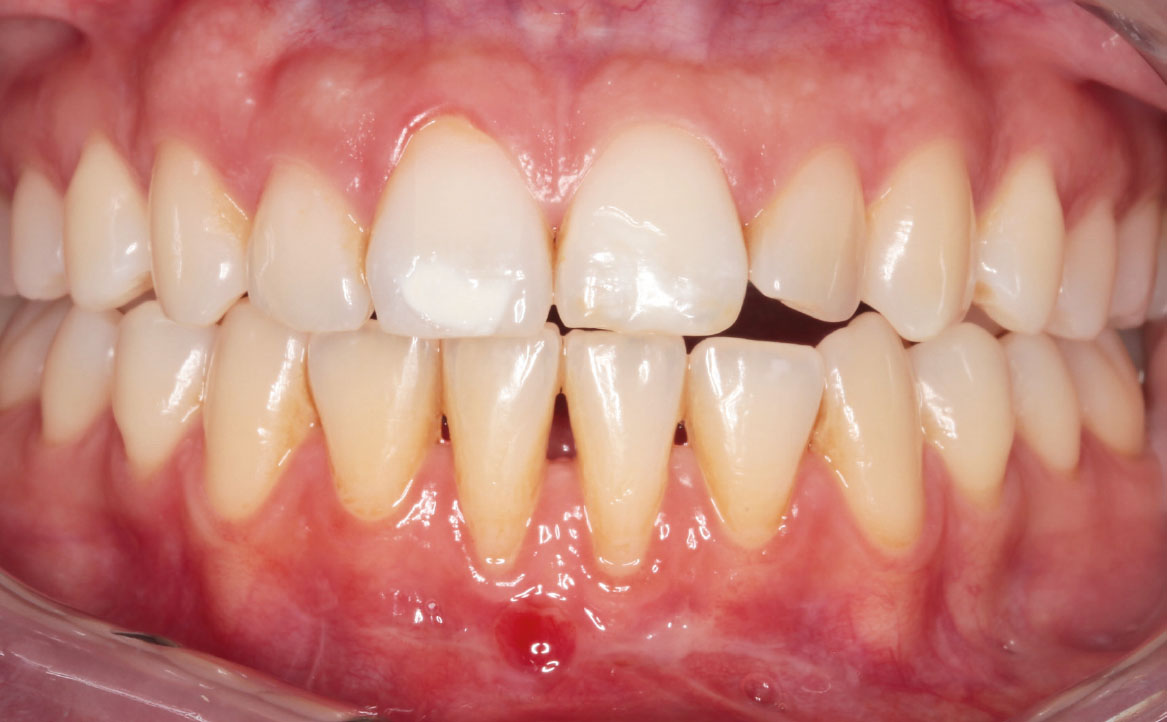

A tre mesi si osserva una completa e ottimale guarigione della ferita chirurgica (fig. 15).